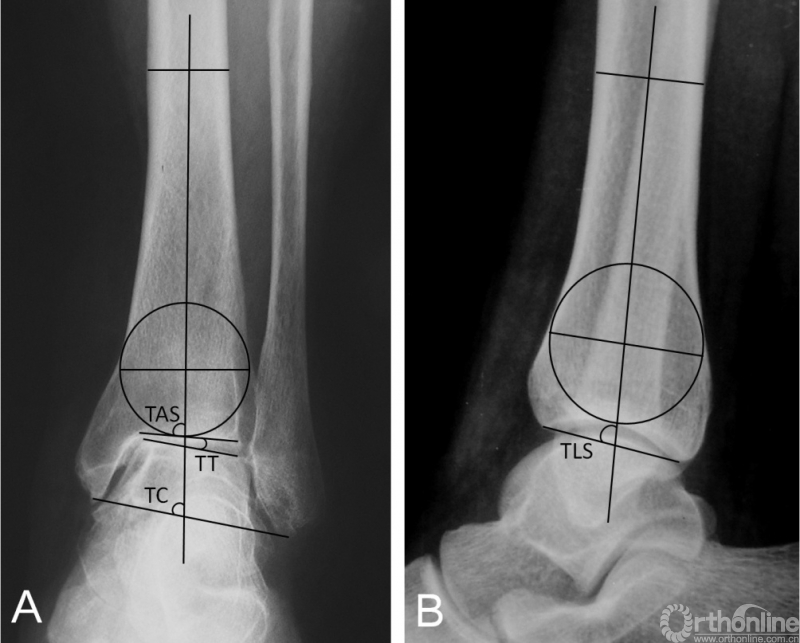

临床评估内容包括术前及末次随访的美国足踝骨科协会(American orthopedic foot and ankle society,AOFAS)踝与后足评分、Maryland足部评分踝关节骨关节炎量表(Ankle Osteoarthritis Scale,AOS)进行临床评估[25],并测量比较踝关节活动度(Range of Motion,ROM)。为了便于量化统计,将改良Takakura分期的2、3A、3B及4期分别赋值为2、3、4、5。影像学测量内容包括胫骨前侧关节面角(tibial anterior surface angle,TAS)、距骨倾斜角(talar tilt angle,TT)、胫骨踝穴角(tibiocrural,angle,TC)以及胫骨侧位关节面角(tibial lateral surface angle,TLS)(图1)。

图1 踝关节前后位X线片(1A):TAS,胫骨前侧关节面角;TT,距骨倾斜角;TC,胫骨踝穴角。踝关节侧位X线片(1B):TLS胫骨侧位关节面角。